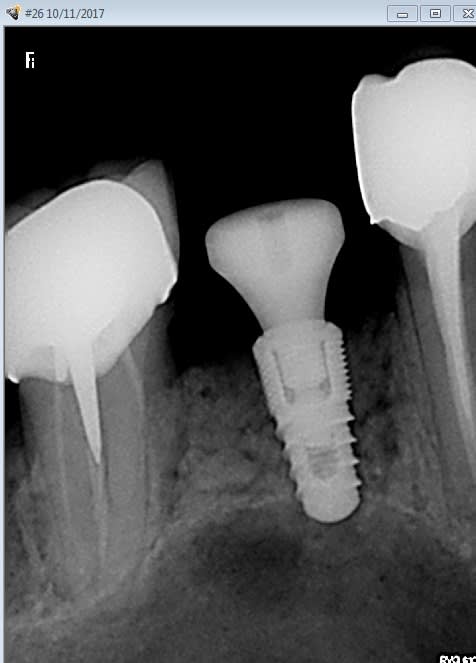

Mise en place d'un naturall + ETK 4 x 8.

Dispo : 6 mm : arret du forage a 5 , puis foret "versah" , on sent bien quand on passe la corticale du sinus.

Verification quand meme de l'étanchéité, un peu bout de PRF au fond et c'est bon.